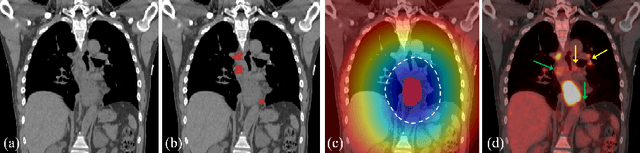

Abstract:Finding, identifying and segmenting suspicious cancer metastasized lymph nodes from 3D multi-modality imaging is a clinical task of paramount importance. In radiotherapy, they are referred to as Lymph Node Gross Tumor Volume (GTVLN). Determining and delineating the spread of GTVLN is essential in defining the corresponding resection and irradiating regions for the downstream workflows of surgical resection and radiotherapy of various cancers. In this work, we propose an effective distance-based gating approach to simulate and simplify the high-level reasoning protocols conducted by radiation oncologists, in a divide-and-conquer manner. GTVLN is divided into two subgroups of tumor-proximal and tumor-distal, respectively, by means of binary or soft distance gating. This is motivated by the observation that each category can have distinct though overlapping distributions of appearance, size and other LN characteristics. A novel multi-branch detection-by-segmentation network is trained with each branch specializing on learning one GTVLN category features, and outputs from multi-branch are fused in inference. The proposed method is evaluated on an in-house dataset of $141$ esophageal cancer patients with both PET and CT imaging modalities. Our results validate significant improvements on the mean recall from $72.5\%$ to $78.2\%$, as compared to previous state-of-the-art work. The highest achieved GTVLN recall of $82.5\%$ at $20\%$ precision is clinically relevant and valuable since human observers tend to have low sensitivity (around $80\%$ for the most experienced radiation oncologists, as reported by literature).

Abstract:Finding and identifying scatteredly-distributed, small, and critically important objects in 3D oncology images is very challenging. We focus on the detection and segmentation of oncology-significant (or suspicious cancer metastasized) lymph nodes (OSLNs), which has not been studied before as a computational task. Determining and delineating the spread of OSLNs is essential in defining the corresponding resection/irradiating regions for the downstream workflows of surgical resection and radiotherapy of various cancers. For patients who are treated with radiotherapy, this task is performed by experienced radiation oncologists that involves high-level reasoning on whether LNs are metastasized, which is subject to high inter-observer variations. In this work, we propose a divide-and-conquer decision stratification approach that divides OSLNs into tumor-proximal and tumor-distal categories. This is motivated by the observation that each category has its own different underlying distributions in appearance, size and other characteristics. Two separate detection-by-segmentation networks are trained per category and fused. To further reduce false positives (FP), we present a novel global-local network (GLNet) that combines high-level lesion characteristics with features learned from localized 3D image patches. Our method is evaluated on a dataset of 141 esophageal cancer patients with PET and CT modalities (the largest to-date). Our results significantly improve the recall from $45\%$ to $67\%$ at $3$ FPs per patient as compared to previous state-of-the-art methods. The highest achieved OSLN recall of $0.828$ is clinically relevant and valuable.